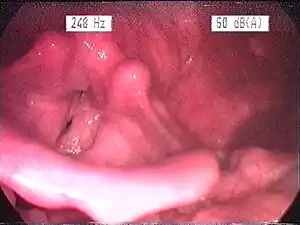

| Endoscopic image of an inflamed larynx caused by acid reflux | |

The larynx itself will often show erythema (reddening) and edema (swelling). This can be seen with laryngoscopy or stroboscopy (method depends on the type of laryngitis).[7]: 108 Other features of the laryngeal tissues may include

- Redness of the laryngeal tissues (acute)

- Dilated blood vessels (acute)

- Thick, yet dry laryngal tissue (chronic)

- Stiff vocal folds

- Sticky secretions between the vocal folds and nearby structures (the interarytenoid region)